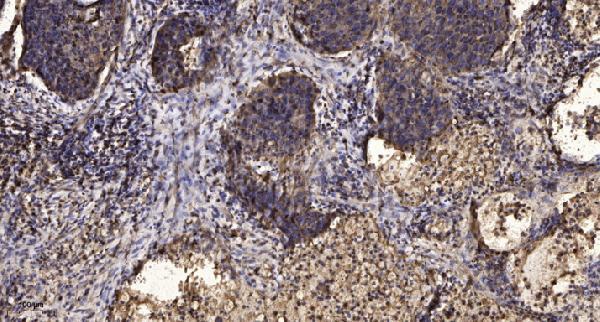

Facts about Melatonin receptor type 1A.

| Gene Name: | MTNR1A |